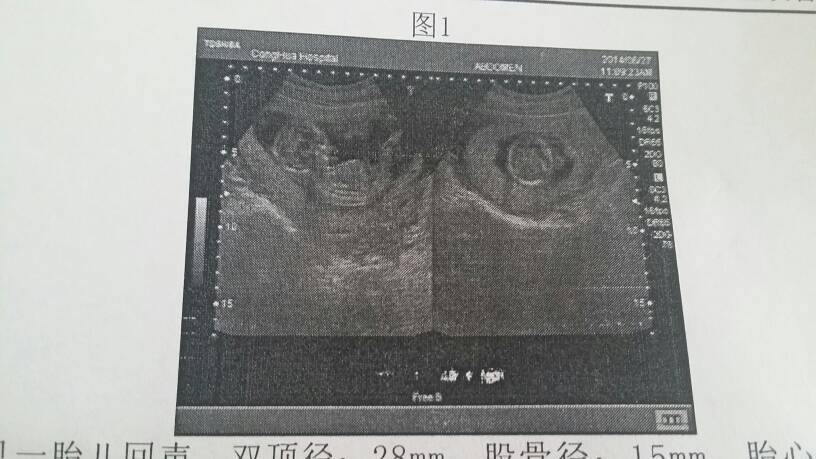

今天第一次产检,因为在百度上查说做唐氏筛查要空腹的,所以没吃早饭就到了医院挂号(突然觉得大肚子可真多.可能以前从没留意过吧)后来医生说不用空腹,我和肉丸子就去吃了老M,吃过早饭后医生说我时间比较短在过两周做唐氏,现在是15+2.今天在医生的建议下建了产检卡,查了好多项目[失望]抽血(抽了俺7罐子的血)[泪]尿检,白带,心电图,B超,还有第一次听见宝宝的心跳好激动[太开心][太开心]听胎心的时候他还突然调皮的跑到另一边[抱抱][抱抱],照B超时候都能看出宝宝成形了,很好奇k是男孩还是是女孩,问了两次医生就是不说,我的好奇心太重了,就是想知道男孩还有女孩[抱抱]看来要去私人医院请人家看了